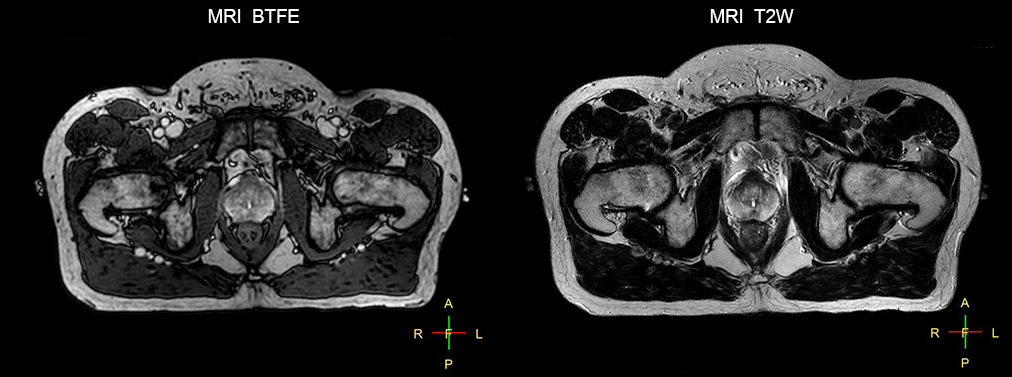

“The biggest problem for CT-based planning, especially in prostate, is you can’t see the cancer very well,” says Dr. Stevens. “On CT it can be quite challenging to see the edge of the prostate especially at the apex. When the edge of the prostate can’t be delineated well on CT, radiation oncologists will increase their margins a little bit so they don’t miss it, but that can also increase toxicity.” “Using MR, the prostate is well delineated. We quickly see the edges of cancerous tumors like in prostate cancer, and as normal structures can be defined, we can optimize the treatment plan to protect these organs and their normal function. This can potentially improve the outcome. And it improves workflow as well. We can contour more quickly, confident that the tumor is going to be in the field.” “The Ingenia 3.0T MR scanner provides high resolution allowing us to make scans fast for the patients. It also gives the potential to include methods like MR spectroscopy and diffusion weighted Imaging, which we’re in the process of doing right now,” Dr. Stevens adds.

Beaumont Health System (Royal Oak, Michigan, USA) is one of the largest health systems in the USA, with eight hospitals and 153 outpatient sites, a medical school and a research institute. The Radiation Oncology (RO) department houses a dedicated Ingenia MR-RT solution that is routinely used for clinical and research MR-RT activities. “The main reason to integrate MR imaging in RT planning is the superb soft tissue contrast that allows detailed delineation of tumors and healthy organs, which is crucial for RT planning,” says Craig W. Stevens MD, PhD. “MR also provides information on functional and biological activities in tumors, background tissue and normal organs, which may also be used in RT planning,” says physicist Di Yan, DSc, FAAPM.” “We currently use MR-RT mainly in the abdomen and pelvis region: prostate, colorectal, pancreatic, cervical, and liver. Also in the brain, we are starting to use it,” says Dr. Yan.

“There are some general challenges in RT imaging – even with CT – such as imaging geometry and positioning accuracy. Positioning is extremely important in RT, because we need reproducibility between imaging and treatment position. We also need accurate geometry so we can be sure our treatment plan is properly delivered during the treatment,” says Dr Yan. “The Ingenia MR-RT configuration includes an external laser positioning system for patient alignment and a flat tabletop for imaging the patient in treatment position. Ingenia MR-RT also came with a special QA package for regular monitoring of precision. Our Ingenia 3.0T scanner achieves good geometric accuracy – within a millimeter for most patients – and the phantom measurement is even better,” he adds. “Ingenia’s wide 70 cm bore is valuable to easily accommodate immobilization devices needed in RT,” says Dr. Stevens. “With a small bore MR scanner you can’t get the RT immobilization devices into the scanner properly; the large bore makes it easy to image patients in their immobilization device.”